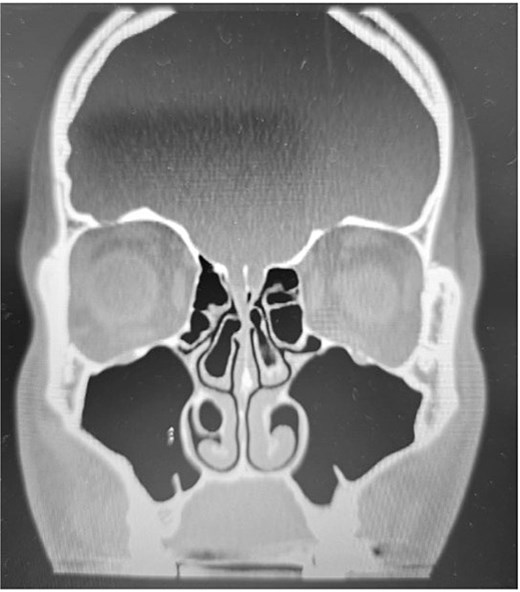

Clinical examination, including anterior rhinoscopy and nasal endoscopy, revealed a midline nasal septum and bilateral hypertrophy of the inferior and middle turbinates, with otherwise normal nasal mucosa. A CT scan of the paranasal sinuses in the coronal plane demonstrated bilateral pneumatization of the middle turbinates consistent with CB. Additionally, the right inferior turbinate was pneumatized, with communication to the ipsilateral maxillary sinus (Figs 1 and 2).

Paranasal sinus CT scan in the coronal plane showing bilateral concha bullosa in the superior turbinates and pneumatization of the right inferior turbinate (inferior concha bullosa).